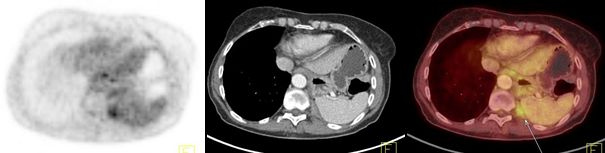

Los carcinomas tímicos (figs. 3, 4 y 5) se destacaron por un elevado metabolismo, con un SUVmax promedio de 10,4 (rango 5,6 a 13,2) y presentaron contornos irregulares, con compromiso de la grasa y de estructuras vecinas, presencia de calcificaciones, parálisis frénica (6 casos en 7) y siembra o derrame pleural o pericárdico (4 casos en 7).

Los linfomas exhibieron captación de 18FDG uniformemente elevada, con SUVmax promedio de 15,4 (rango 15,2 a 15,7). Uno de ellos presentó compromiso local de la pared torácica.

Tanto los linfomas como los carcinomas y timomas de alto grado se asociaron con la presencia de adenopatías hipermetabólicas. No se comprobaron metástasis extratorácicas en esta serie.